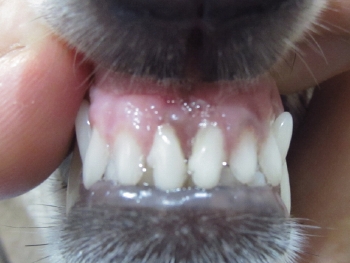

歯石除去 例2